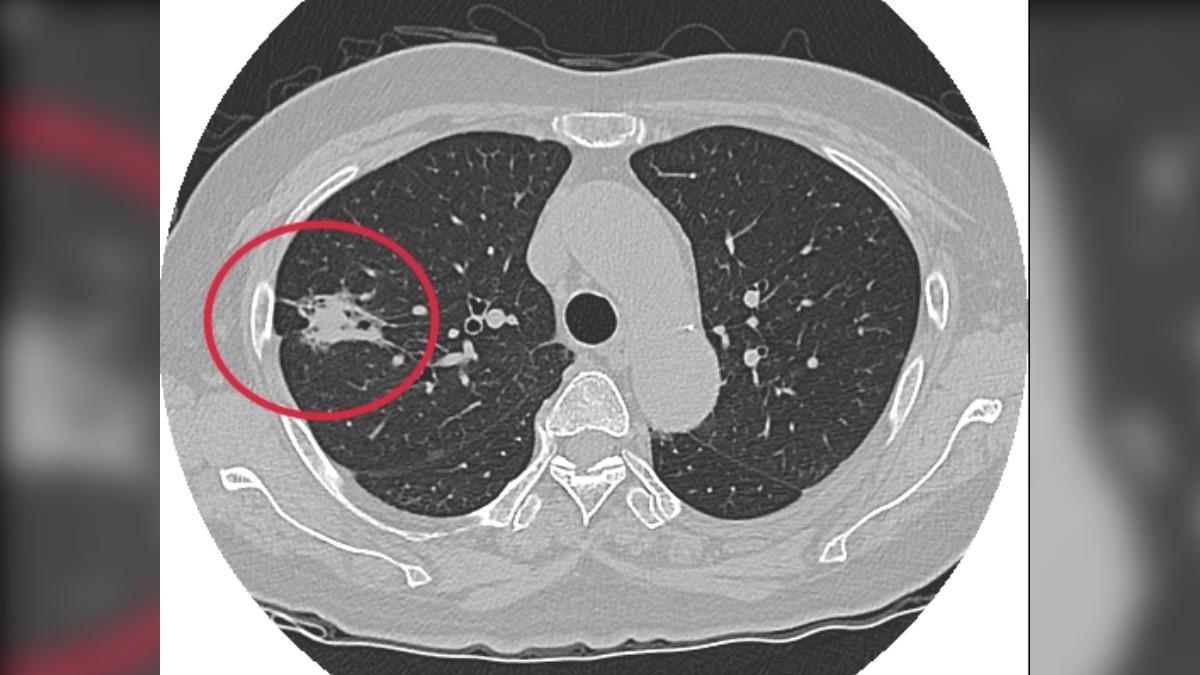

呂庭聿說明,李嬤2015年接受健康檢查時,在右肺發現結節,當時研判可能為良性,但得每年追蹤,期間李嬤沒有任何身體不適症狀,還常笑說「自己比正常人還正常」,未料2023年結節惡化為近3公分腫瘤,並且是惡性的第一期肺腺癌。

而呂庭聿提醒,肺癌可分為「小細胞肺癌」和「非小細胞肺癌」,是全球及台灣癌症死因第一,其中「肺腺癌」是「非小細胞肺癌」中最常見的癌,不抽菸也可能得到,同時為女性最好發肺癌類型,若不盡快動手術,拖到第三或第四期,不僅擴散速度快,末期存活率不到10%。